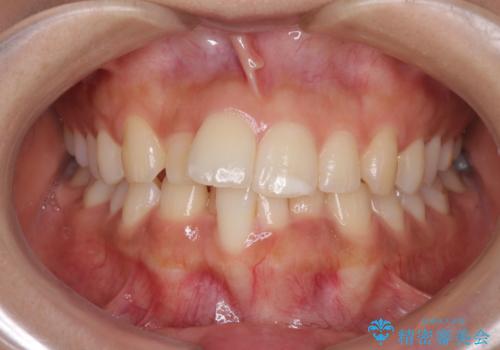

- 飛び出した前歯と全体的なデコボコを気にして来院された患者様です。

ワイヤーでもマウスピースでも治療可能でしたが、自己管理の重要なマウスピース矯正は自分には向かないとのことで、ワイヤー矯正で治療することとしました。